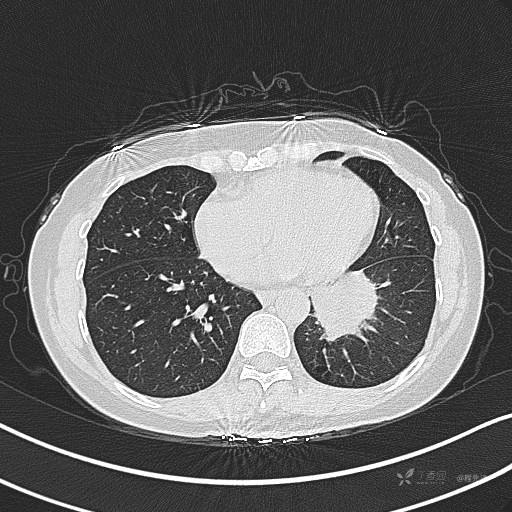

CT平扫

肺窗